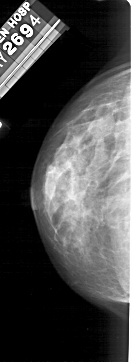

A_1497_1.LEFT_CC

LEFT_CC LINES 5056 PIXELS_PER_LINE 1846 BITS_PER_PIXEL 12 RESOLUTION 43.5 NON_OVERLAY